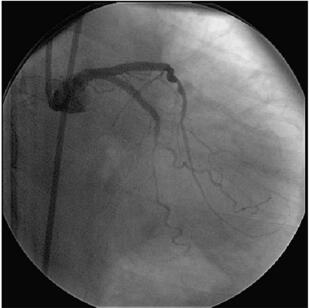

冠状动脉造影(图058‐2、图058‐3)多体位造影显示:冠脉呈右冠优势型,L M开口见90%局限性狭窄;LAD 管壁不光滑,近段见90%局限性狭窄,D1 开口后次全闭塞,中段见85%弥漫性病变,远端血流TI MI 3 级;LCX 管壁不光滑,远端90%局限性狭窄,OM1分叉处Ⅰ型分叉病变,最窄处约80%,远端血流TI MI 3 级;RCA 管壁欠光滑,远段见85%偏心性狭窄,PDA 开口前分叉病变,最窄处约95%,远端血流TI MI 3 级。

图058‐2 冠状动脉造影

图058‐3 冠状动脉造影